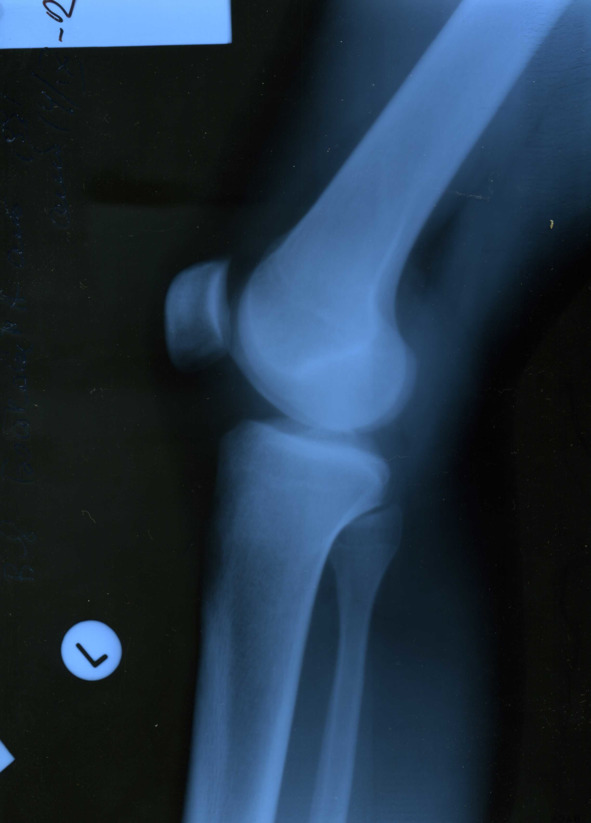

В сентябре 2012 года, когда уже оба сустава по кругу обострялись ни один раз, в очередной раз случилось обострение, и я все-таки решил обратиться к коллеге-хирургу за обследованием и профессиональной помощью. После общего осмотра было назначено рентген-обследование коленных суставов (все снимки представлены ниже).

Изменения малозаметны, но все же диагноз хронический остеоартроз подтвердил врач-рентгенолог, хирургом назначены обезболивающие средства и аппликации сустава димексидом.